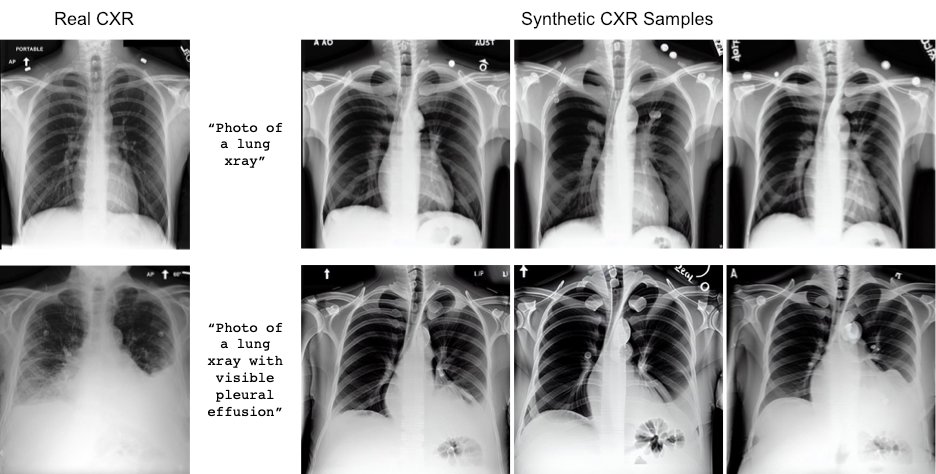

Pierre Chambon et Christian Bluethgen ont découvert que le code open source de Stable Diffusion pourrait être efficace pour créer des imageries médicales. Les modèles de base ne donnent pas de bons résultats pour les demandes spécifiques car leurs bases de données sont trop génériques. Mais en utilisant des données d’entraînement provenant des rapports textuels des radiologues, ils ont réussi à générer leurs premières radiologies de poumons humains avec des anomalies.

Les chercheurs ont expérimenté plusieurs tests et ont fait évaluer leurs résultats par leurs collègues radiologues. Ils ont découvert que leur modèle de deep learning, appelé RoentGen, pouvait reproduire une anomalie dans une image radiologique synthétique avec une précision de 95 %. L’équipe a ensuite intensifié ses efforts de formation en utilisant des dizaines de milliers de radiographies pulmonaires et les rapports correspondants. Désormais, le modèle peut créer des images de radiographies pulmonaires avec une plus grande fidélité et une diversité accrue. Il permet également un contrôle plus fin des caractéristiques de l’image, comme la taille et la disposition des poumons.